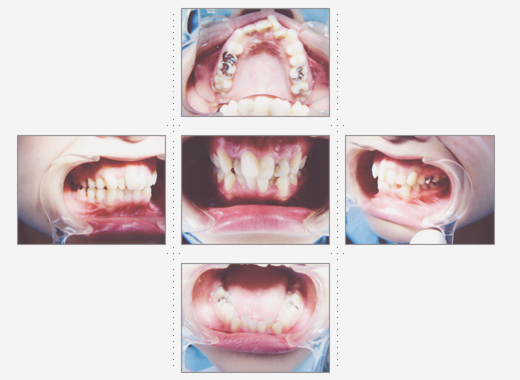

症例1

理学療法士 36才 女性

上下の歯並びを直したいというご希望で、来院。

術前と術後では、歯並び表情が変わった事はもちろんのこと、顔の形も変わり、「美容整形をしたように小顔になれました」と喜んでいただけました。